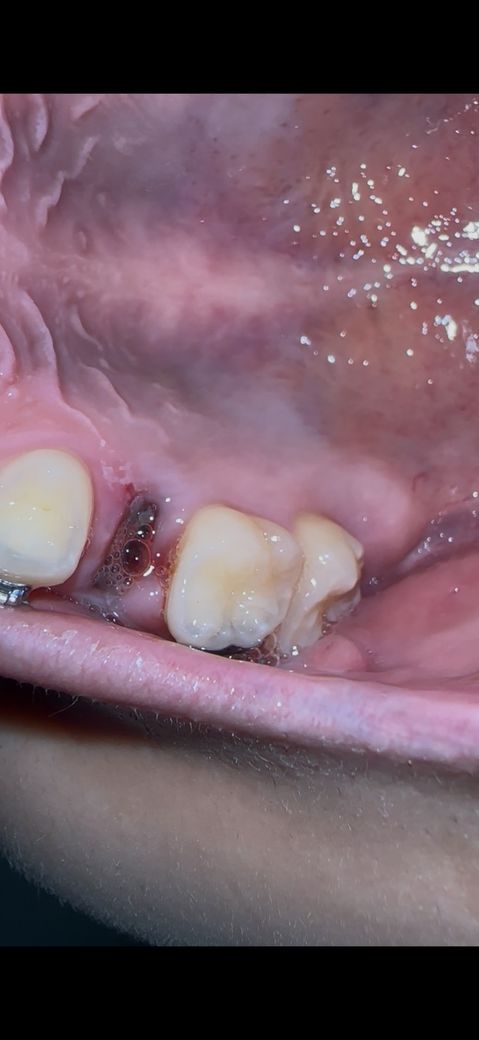

1월 6일날 발치했고 잘 아물어가는지 궁금해요

통증은 없고

몰랐는데 사진으로보니 침이 많이 고여있네요

아물어가는 과정이려나요 ?

• 2번 째 사진

발치한 부위는 문제가 없이 잘 아물고 있는것으로 보입니다.

너무 걱정하지 않아도될것으로 생각됩니다.

발치한 부위가 아물기 위해서는 해당부위가 자극되지 않도록 하는것이 좋습니다.